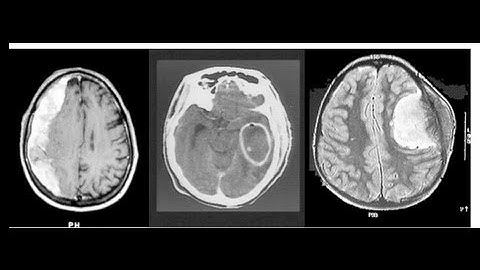

Stroke Mimics and TPA